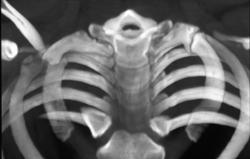

GSW to Scapula W/fracture